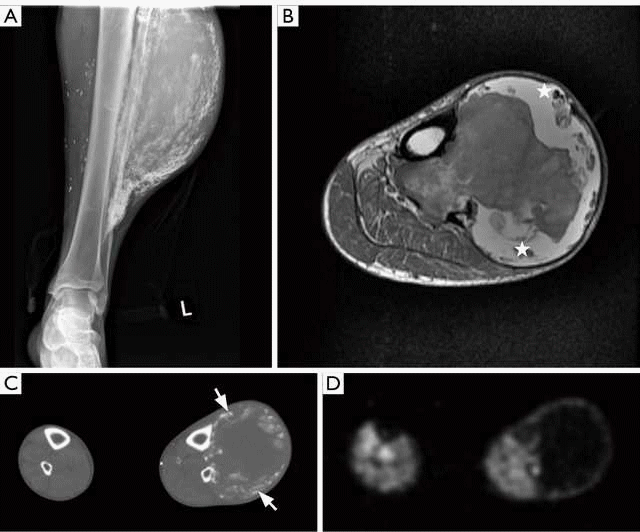

Chụp cộng hưởng từ MRI phần mềm là kỹ thuật được ưu tiên lựa chọn trong chẩn đoán các bệnh lý xương và mô mềm. Qua hình ảnh chụp MRI, các mô mềm được hiển thị rõ nét, giúp các bác sĩ phát hiện các tổn thương ác tính, đồng thời đánh giá mức độ lan rộng của các tổn thương nhằm đưa ra kế hoạch điều trị thích hợp.

- Khối u mô mềm: Phát hiện, mô Tả các đặc tính và loại trừ khối u; Sinh thiết, đánh giá khối u; Điều trị và theo dõi sau điều trị.